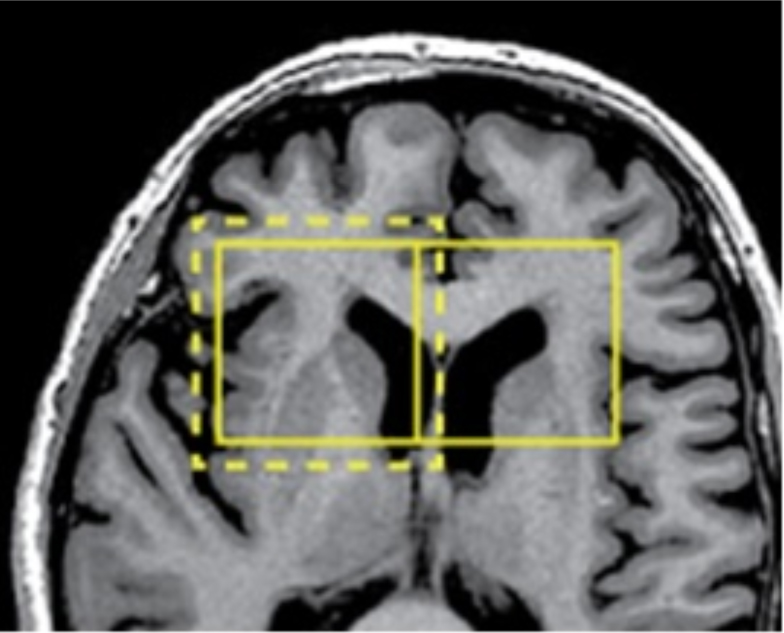

Finally, we decided to use a filter that only needs the information of some neighboring pixels (see Figure 1): The Smoothing Recursive Gaussian Image Filter of ITK [12]. This filter generates a smooth image by performing a convolution on it, which uses a kernel with values given by the Gaussian distribution. The result of this algorithm can be observed in Figure 2 on a magnetic resonance of a brain.

Application of the Smoothing Recursive Gaussian Image Filter. Left: Original image. Right: Blurred image after applying the filter.